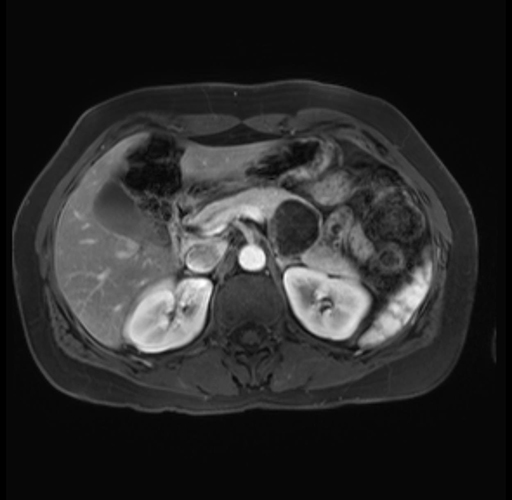

Imaging Analysis

Look through the patient's CT scan to identify any areas of concern for the necessary procedure.

Based on your CT findings, which issue(s) are present and would give reason for "planned slowing down moment(s)" in this case?

Considering a standard distal pancreatectomy procedure, what step(s) of the operation would you do differently in this case?